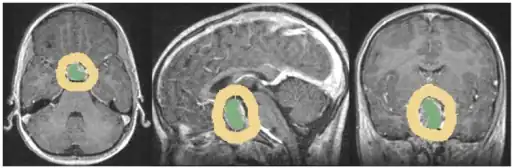

The differential diagnosis includes pituitary tuberculoma, especially in developing countries and in immumocompromised patients.[46] The diagnosis is confirmed by testing hormone levels, and by radiographic imaging of the pituitary (for example, by CT scan or MRI).

- Anatomically pituitary tumors are classified by their size based on radiological findings; either microadenomas (less than <10 mm) or macroadenomas (equal or greater than ≥10 mm).

Pituitary incidentalomas are pituitary tumors that are characterized as an incidental finding. They are often discovered by computed tomography (CT) or magnetic resonance imaging (MRI), performed in the evaluation of unrelated medical conditions such as suspected head trauma, in cancer staging or in the evaluation of nonspecific symptoms such as dizziness and headache. It is not uncommon for them to be discovered at autopsy. In a meta-analysis, adenomas were found in an average of 16.7% in postmortem studies, with most being microadenomas (<10mm); macrodenomas accounted for only 0.16% to 0.2% of the decedents.[2] While non-secreting, noninvasive pituitary microadenomas are generally considered to be literally as well as clinically benign, there are to date scant studies of low quality to support this assertion.[54]

It has been recommended in the current Clinical Practice Guidelines (2011) by the Endocrine Society - a professional, international medical organization in the field of endocrinology and metabolism - that all patients with pituitary incidentalomas undergo a complete medical history and physical examination, laboratory evaluations to screen for hormone hypersecretion and for hypopituitarism. If the lesion is in close proximity to the optic nerves or optic chiasm, a visual field examination should be performed. For those with incidentalomas which do not require surgical removal, follow up clinical assessments and neuroimaging should be performed as well follow-up visual field examinations for incidentalomas that abut or compress the optic nerve and chiasm and follow-up endocrine testing for macroincidentalomas.[55]